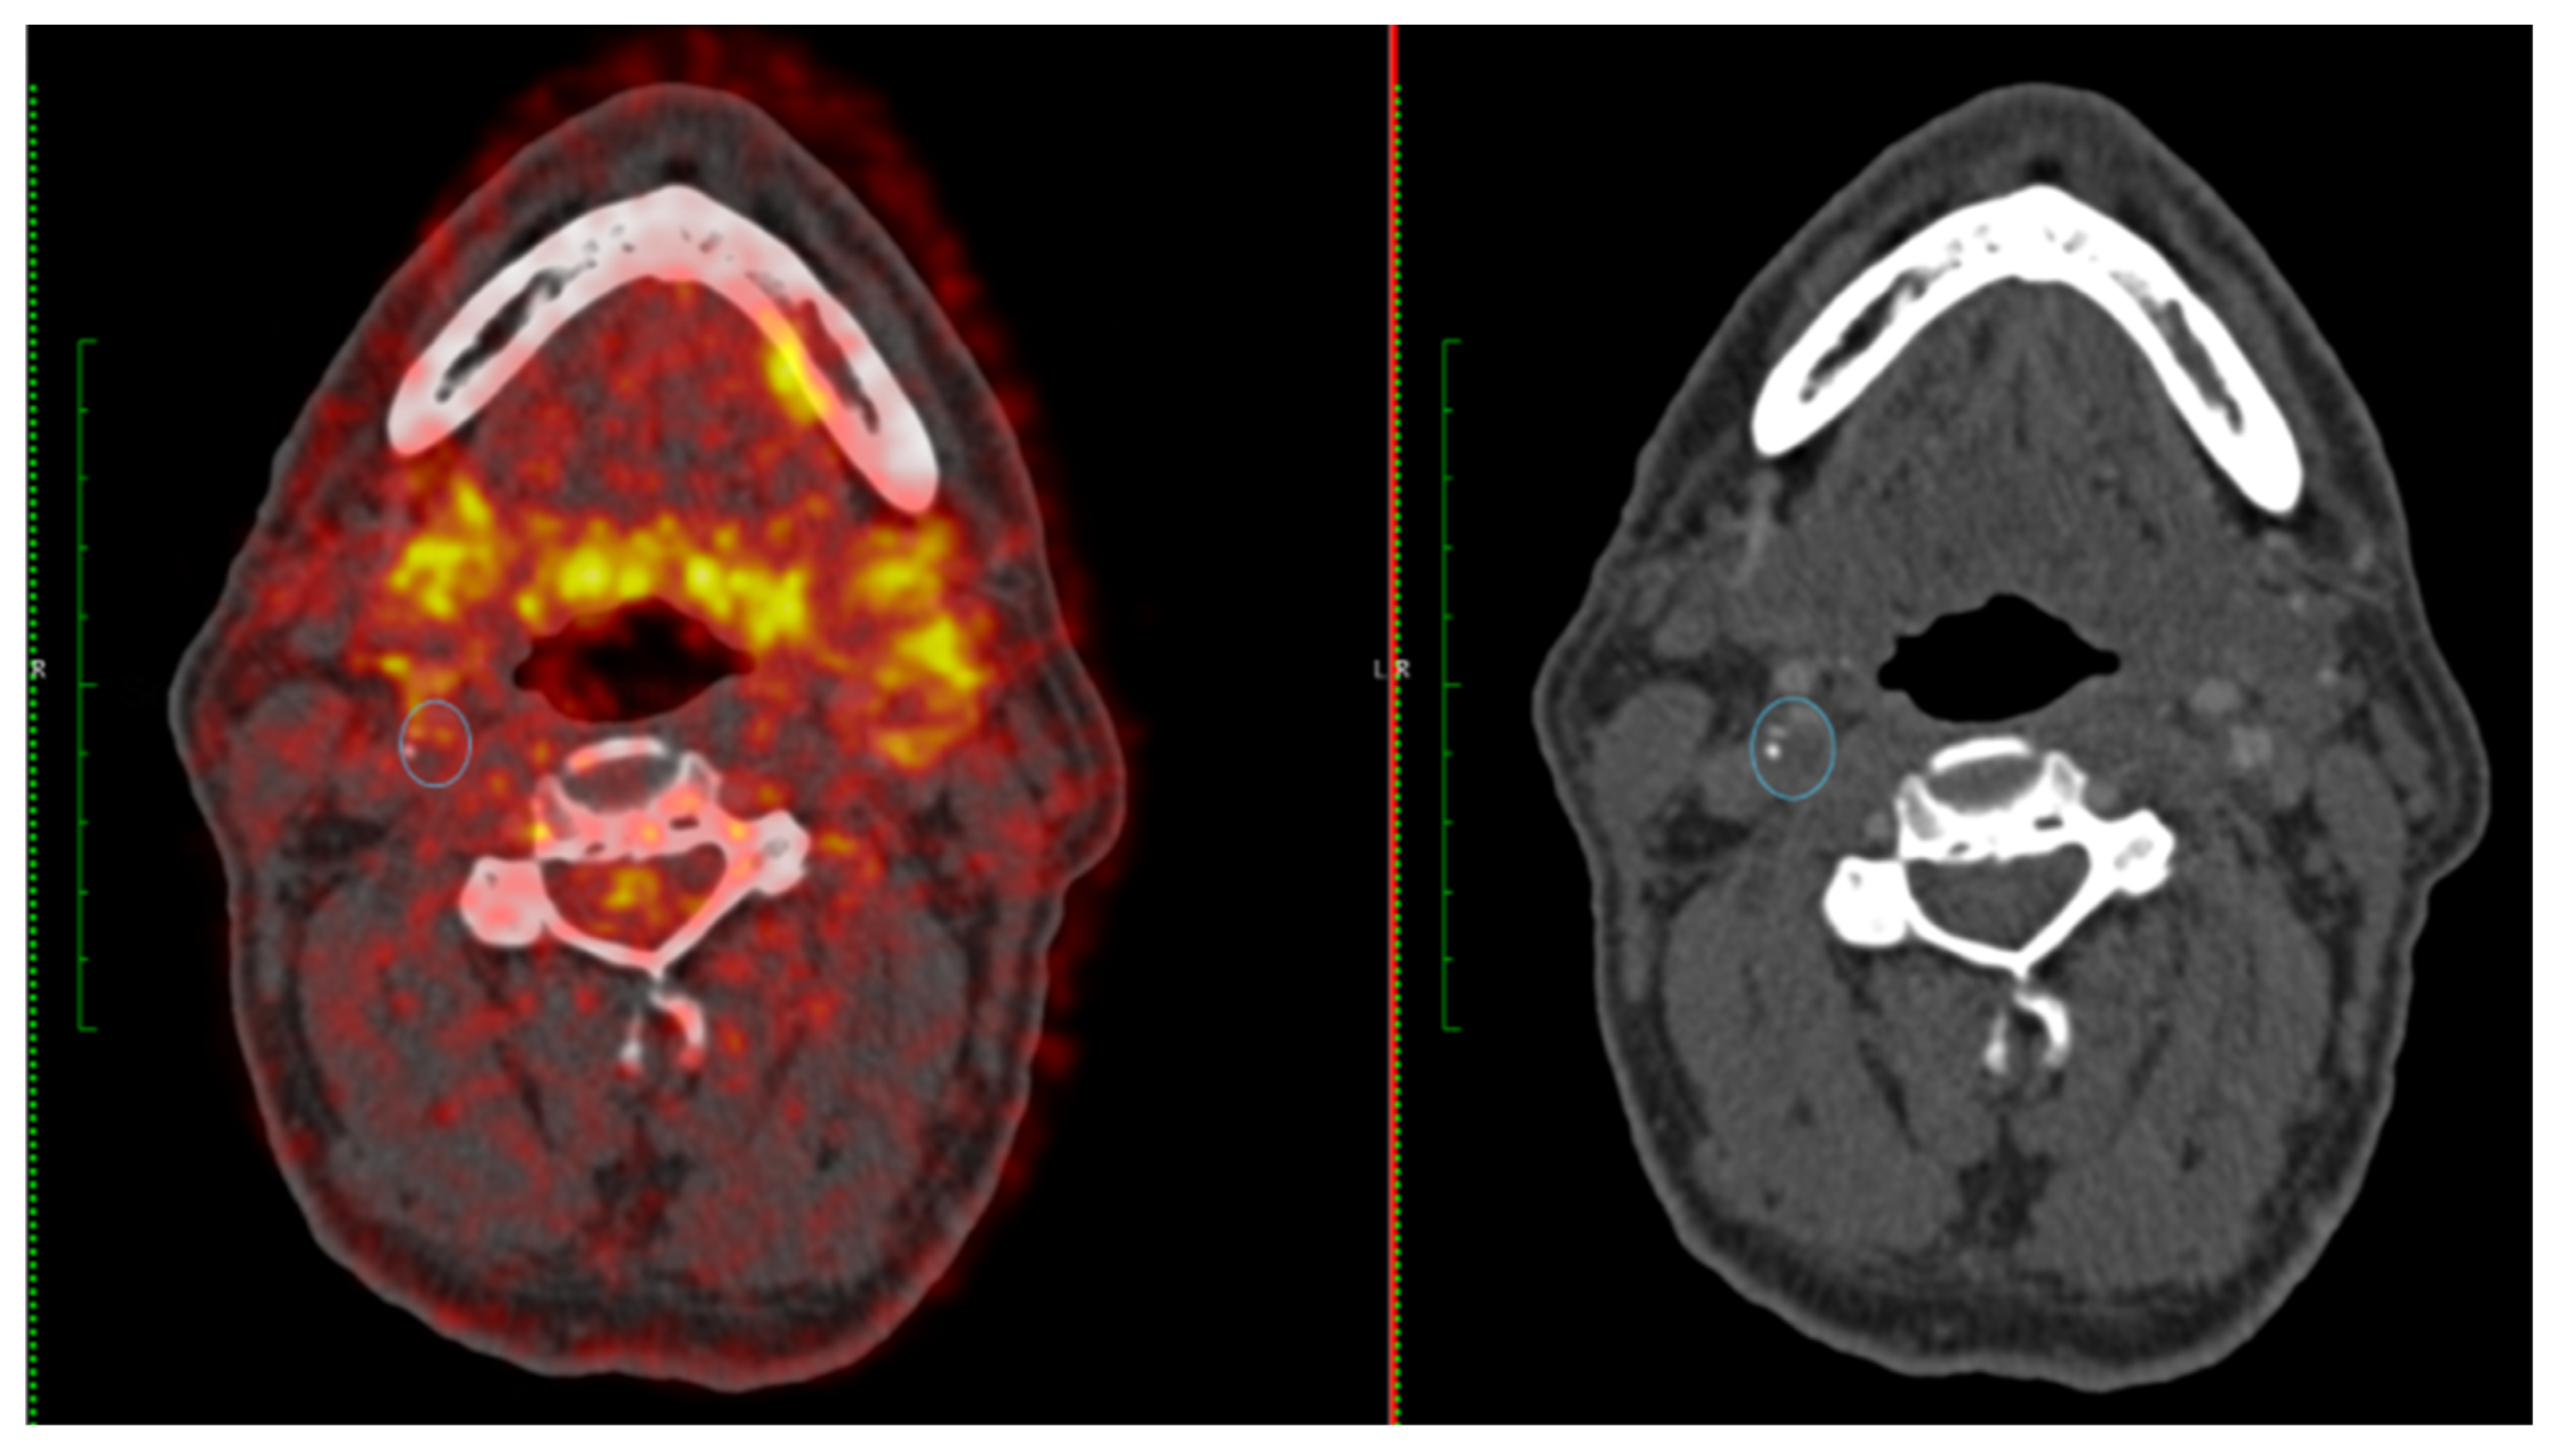

Figure 3.

A 65-year-old female with right-sided amaurosis fugax. Duplex ultrasonography demonstrated a severe right internal carotid artery (ICA) stenosis (70–99%). FDG-PET (left panel) shows moderate FDG uptake in the right ICA (SUVmax 2.45 g/L) and CT angiography confirms a severe stenosis (right panel) (SCAIL score 3).